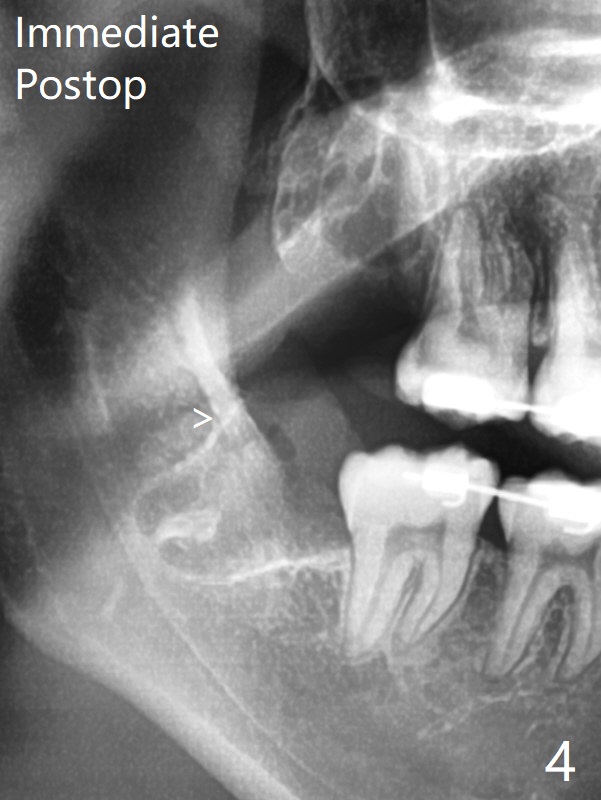

在局麻下拔除4个智齿,由于去骨,显得外斜嵴缺失(图四:箭头),放置胶原塞(防止干槽症),4-0含铬羊肠线缝合,预计外斜嵴6-12月能修复。